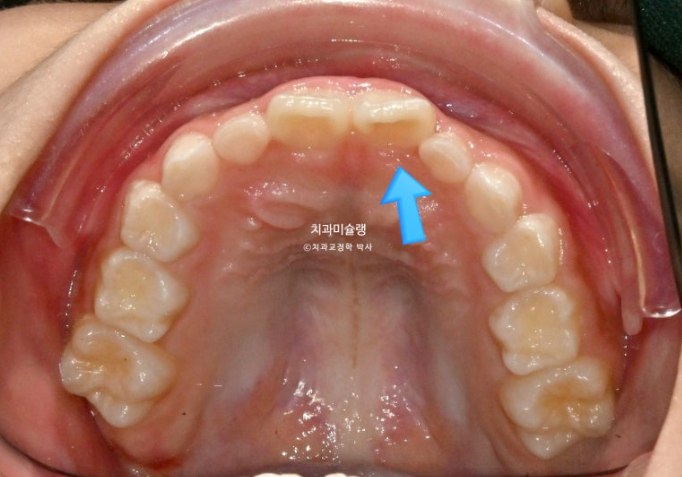

두달 후 앞니 반대교합이 해소가 되어 왔습니다.

25.06

덧니처럼 배열에서 벗어나있던 앞니가 꽤 제자리로 들어온 것이 보이죠?

프리올소는 앞니 배열을 완벽하게 하지는 않지만 약간은 잡아주는 효과도 있습니다.

배열에서 벗어나있던 앞니가 3개월 전에 비해 좀 더 가지런하게 배열이 되어있습니다.